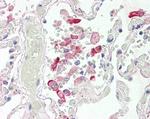

CES1 Polyclonal Antibody

Invitrogen

8

种属

Human Mouse Rat

类型

Rabbit Polyclonal

应用

WB IHC IHC (P) ICC/IF Flow ELISA